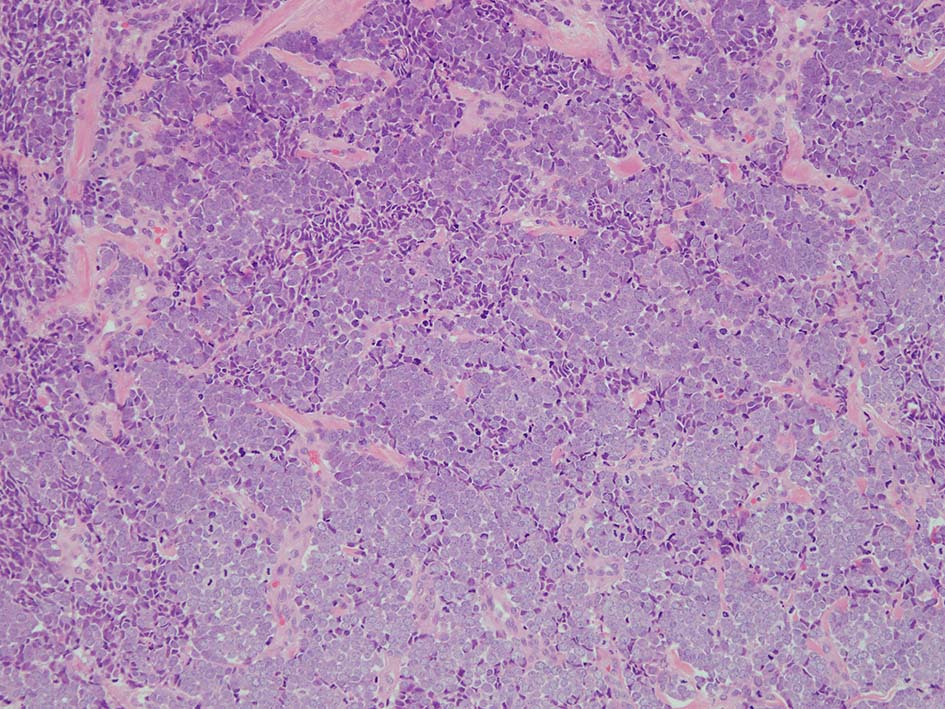

皮膚原発性Merkel細胞癌は 通常真皮を病変首座に増殖し, しばしば脂肪織まで浸潤する.

表皮とは連続性がなくGrenz zoneがみられるのが特徴であるが, 病理所見は多様であり, ときに表皮向性を示す症例やpagetoid patternを呈する症例もある.

典型的な腫瘍細胞は円形, 卵円形の比較的均一な形態で「salt-and-pepper」と称される微細顆粒状クロマチンを有する小型円形核をもつ. MCPyV陽性例が均一な小型円形核を呈する傾向があり, 陰性例では, 核多形性が目立つととする報告がある.

trabecular type, intermediate type, samll cell typeの3パターンの組織型に分類されているがしばしば混在している.

- intermediate typeではtrabecular, samll cell typeの中間の腫瘍細胞サイズを示す. 組織型としてはもっとも多い.

腫瘍内浸潤リンパ球/炎症細胞は多くの症例で認められる. リンパ球の腫瘍内浸潤は予後良好因子と報告されている. 16

loupe像 HE

HE

血管を間質にしてround cellsが索状に増殖する所見. rossett様配列がある. CK20は特徴的な dot-like patternを示す. クリックで大きな画像が見られます.